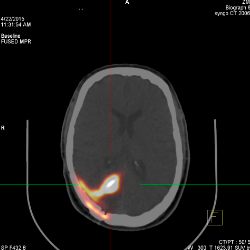

we treat the brain tumor using the latest technologies. Our efforts have saved many lifes and looking forward for many more